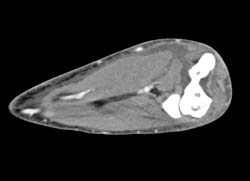

Diagnosis

Cellulitis